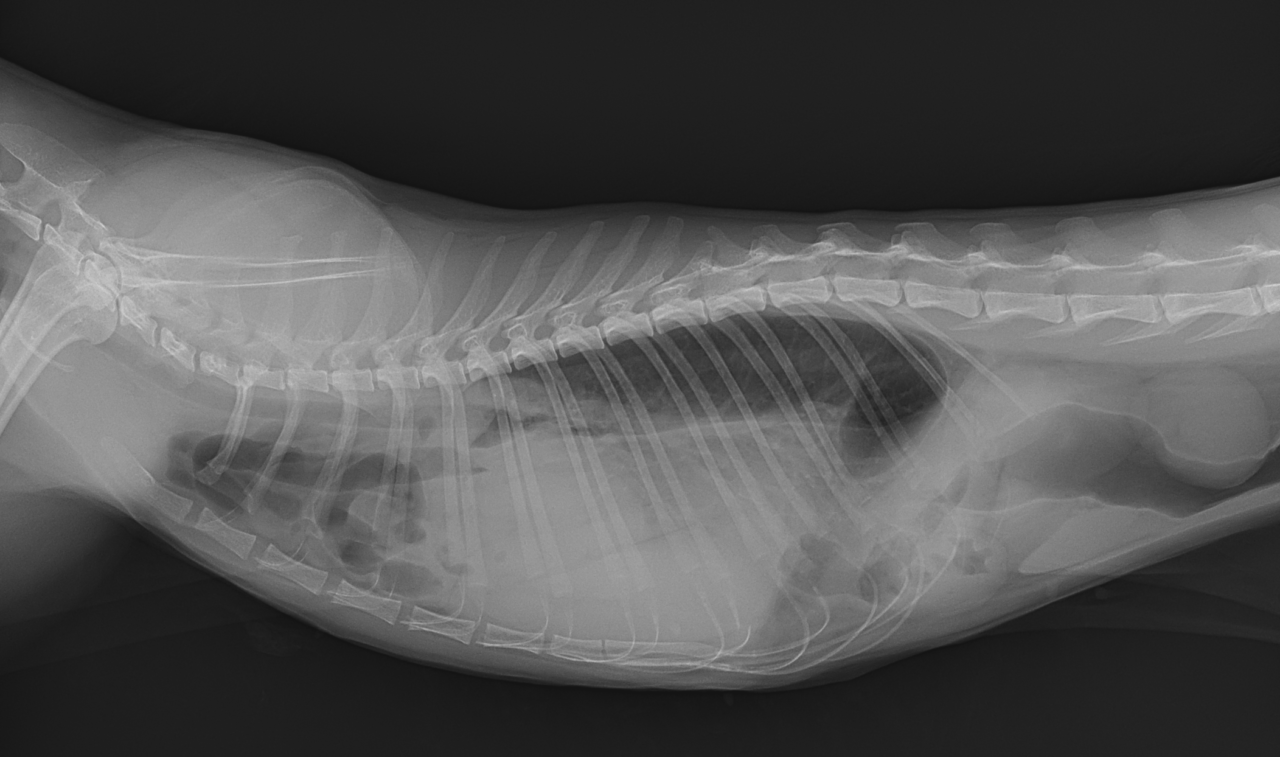

保護した猫さんの呼吸が早いかも??? かかりつけの先生に相談されたようです。エックス線検査で横隔膜ヘルニアが確定されました。外科的な対応を希望され来院されました。肝臓のほとんどが胸腔内にヘルニア(逸脱)しており、開腹アプローチで横隔膜を整復しました。正しい位置に臓器が戻ったので、これからは呼吸が楽になります。